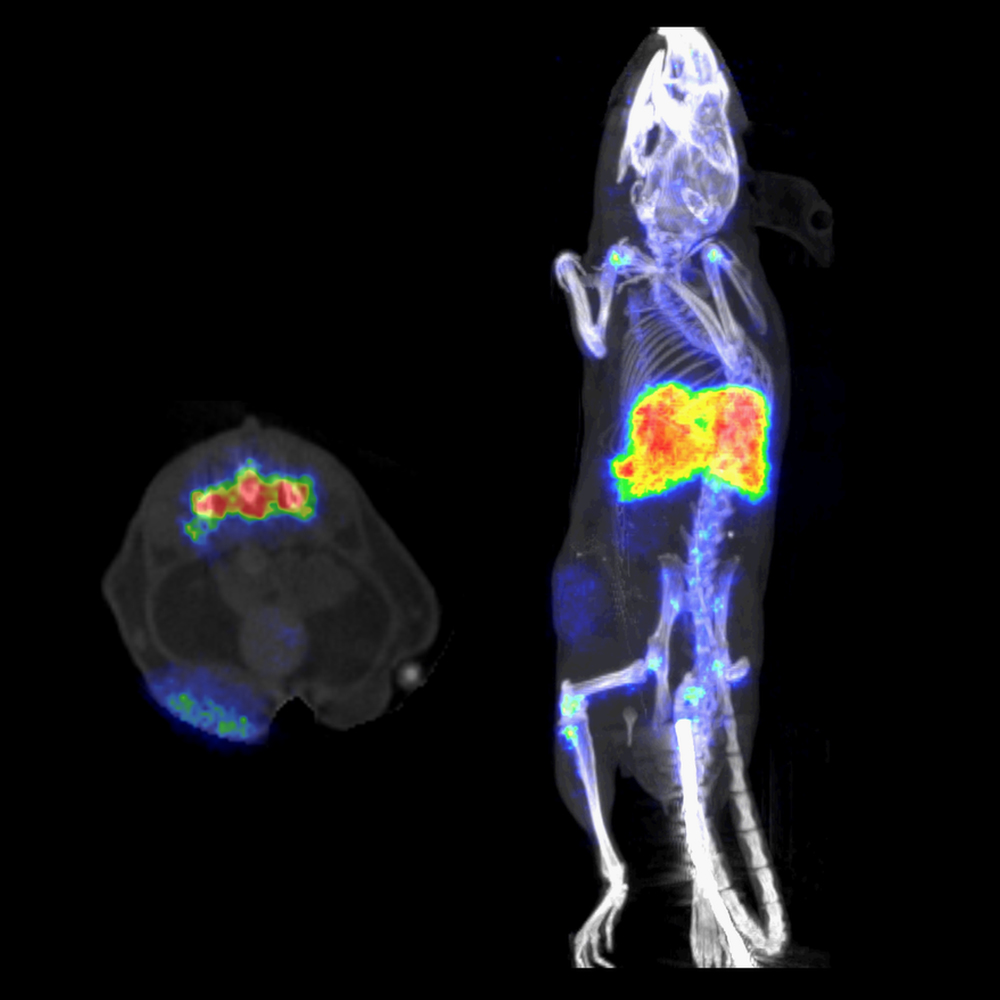

nanoScan® PET システムには、生体内で 700 μm までの高い空間分解能を保証する、最も細い検出器クリスタルニードルが装備されています。

700 μmの空間分解能で細部まで正確に解像

- 高品質なLSOクリスタルニードルにより、生データの空間情報を維持しながら正確な信号位置特定が可能

- リアルタイムのモンテカルロベース物理モデリングによるTera-Tomo™ 3D PET逐次均一画像再構成で、画像の細部まで明らかにすることが可能

- 大きなリング径と統計的DOI補正によって、視野全体にわたって均一な画質を得ることが可能